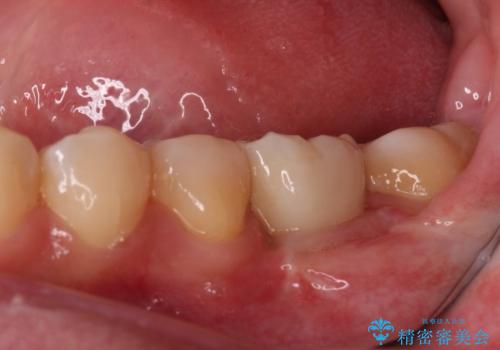

- 放置した虫歯や抜いたままの奥歯、前歯のデコボコを気にして来院された患者様です。

口元の突出感は少なく、下顎の叢生は軽微なものであったので、叢生の強い上顎左右の小臼歯を1本ずつ抜歯し、ワイヤー装置にて矯正治療を行うこととしました。

矯正治療を行う前に、根管治療の必要な上顎前歯と下顎大臼歯の根管治療を行い、矯正治療の途中で下顎の欠損部にインプラント埋入することとし、矯正治療後に補綴治療を行うこととしました。